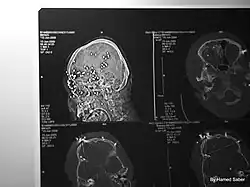

Kinetic-impact-projectiles (KIPs) also known as baton rounds, or rubber/plastic bullets are non-lethal projectiles used for crowd control purposes by riot police.[6][7][1] KIPs are marketed as non or less-lethal weapons used for the purposes of dispersing crowds without causing penetrating wounds.[6] However, when used inappropriately and fired indiscriminately, they have been known to cause injuries leading to life-long disability, or even death.[6][7][8] Examples of KIPs include rubber or plastic bullets, bean bag rounds, sponge rounds (rounds with a softer nose/tip to limit impact) or pellet rounds of birdshot or buckshot.[6][7] Abolfazl Adinezadeh, a 17 year old boy that had joined the Woman, Life, Freedom protests is one of many examples of protesters in Iran who have been killed as a result of close range discharge of KIPs.[8][9] Cases have also been reported in which protesters have either been killed, or lost an eye as a result of being hit directly by tear gas canisters.[7][10][11][12] Abolfazl Amirataie, a 16 year old boy who had joined protests on 22 September 2022 was shot directly in the head at close range with a tear gas canister, causing catastrophic damage to one side of his skull and brain.[10] After 8 months in a vegetative state, Amirataie succumbed to his injuries on 27 May 2023.[10]

"The Mission established that protesters and bystanders, including children who were shot at, including with pellets and rubber bullets, sustained debilitating, severe and painful injuries during protests, which led to disabilities such as blindness. An expert opinion on the physical impact of ammunition such as birdshot and less-lethal weapons commissioned by the Mission highlighted irreversible injures and disabilities that could result from their use. In relation to kinetic impact projectiles specifically, the report highlighted bruising and lacerations of the skin, contusions and fractures of bone and muscle, internal bleeding, liver, heart, and kidney penetration, which could lead to organ failure or death, and neurovascular injuries. Injuries to the head could lead to haemorrhagic strokes and permanent disability while ocular injuries can result to permanent vision loss, given the large size of the projectile against the fragile bony structure and supple eye tissues. The report further stated that metal pellets, which are typically hunting rounds, are “indisputably lethal at close range” and have the ballistic capacity to penetrate some organs, including the eyes causing blindness." Detailed findings, FFM (A/HRC/55/CRP.1), page 155, paragraph 559.[30]